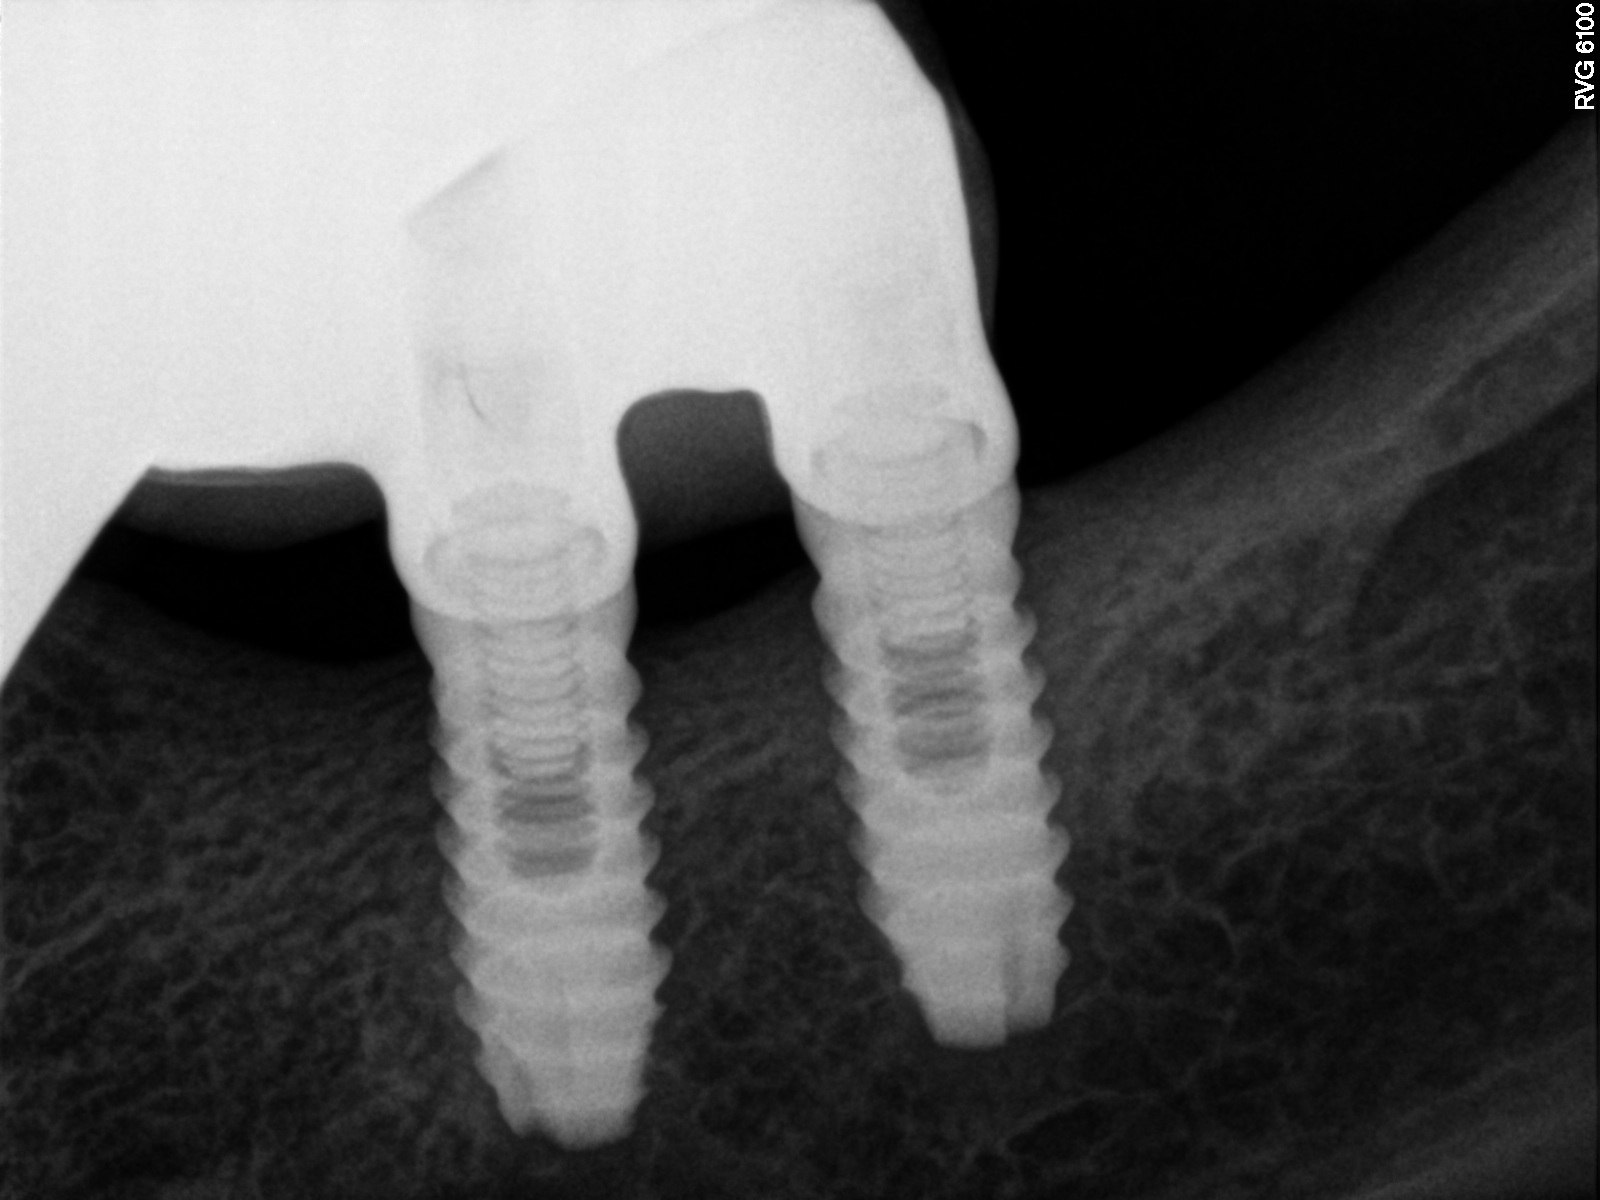

Implantes colocados en clínicas UNIDENTAL, actualmente clínicas Vivanta. La paciente le han dado como nombre de los implante SUAT. ? Alguien sabe que implantes son?. gracias.